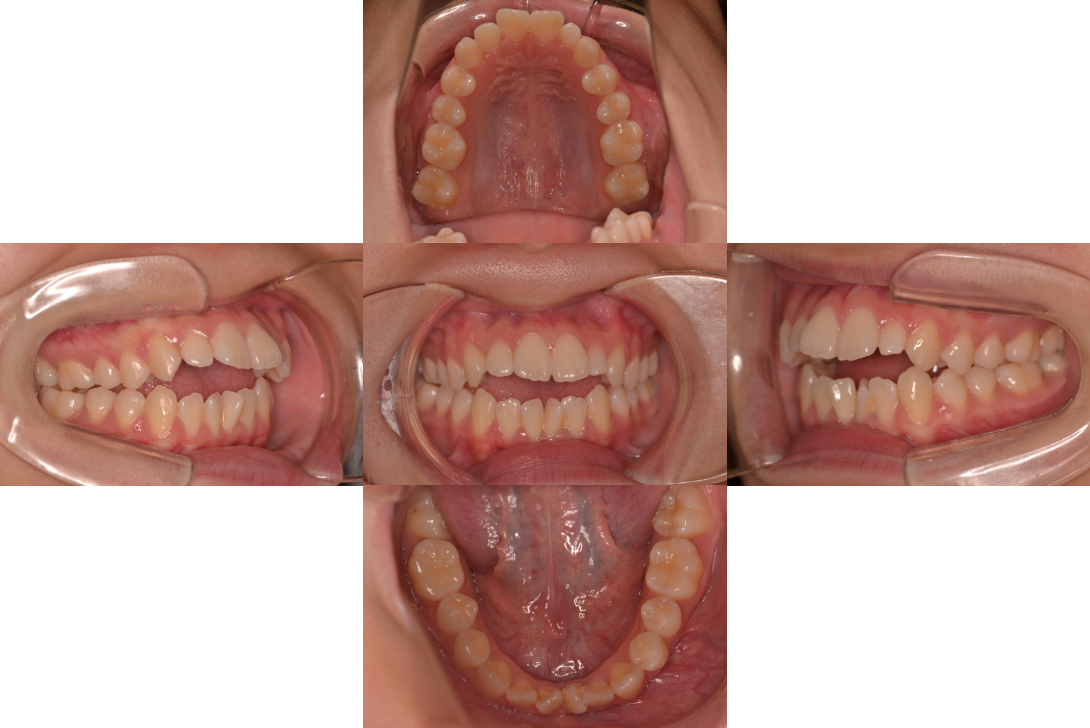

開咬(オープンバイト)を抜歯とDBSで改善した症例

※DBSとはダイレクトボンディングシステムと呼ばれており、ブラケットにワイヤーを通して歯を動かしていく矯正治療です。

患者情報

17歳女性

主訴

ガタガタの歯並びを直したい

行った治療内容

上下顎両側4番抜歯、DBS

治療のリスク

歯肉退縮、歯根吸収

治療期間

動的治療期間4年3か月 (来院がとびとびだった)

※ クリックして拡大することができます。